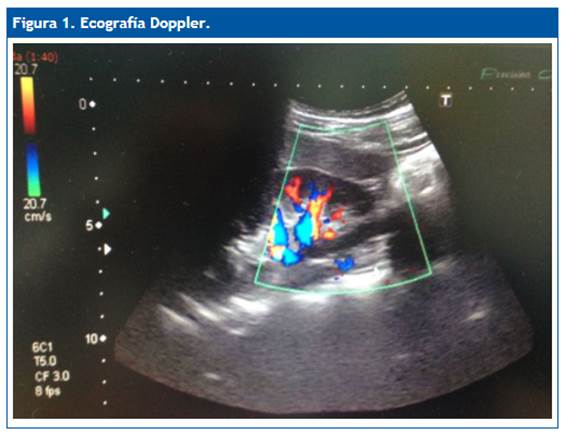

Ante la recurrencia de los episodios y la ansiedad familiar, se decide programar una biopsia renal. Previamente se realiza una ecografía, que detecta la compresión de la vena renal izquierda entre la aorta y la arteria mesentérica superior (Fig. 1 y Fig. 2). Se realiza una angiotomografía renal (Fig. 3) en la que se confirma el diagnóstico de síndrome de cascanueces anterior.

La ecografía Doppler puede ser usada como primera opción ante la sospecha de esta patología. La angiotomografía renal y la angiorresonancia permiten visualizar la anatomía y pueden demostrar con precisión el punto de compresión de la vena renal izquierda y/o la dilatación preestenótica de la vena junto con varices perirrenales o gonadales. La venografía retrógrada es el gold standard del diagnóstico. No solo confirma los cambios anatómicos sino los gradientes de presión. Es la prueba diagnóstica que aporta más información, pero se trata de una prueba invasiva. Solo se realiza si se presentan síntomas graves7,8.